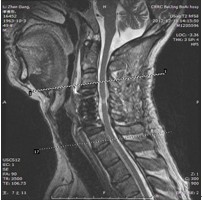

患者,男性,49岁,主因“行走不稳2个月伴右前臂麻木1个月”入院

2月前开始出现双下肢行走不稳,有踩棉花感,行走距离受限。1月前出现右侧前臂及手指麻木感。3周前诊断为“颈椎病”,保守治疗无改善,行走不稳症状加重

影像检查结果:

查体:右侧中指轻触觉、针刺觉减退,左侧上肢及双下肢感觉正常。

肌力:指屈肌群 左/右=5/4级,小指外展肌 左/右=5/4级。双侧膝腱反射亢进。双侧hoffman征阳性。肛门深感觉、自主肛门括约肌收缩存在。